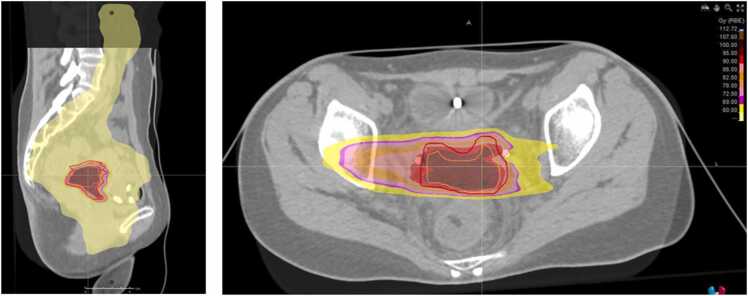

宫颈透明细胞腺癌是一种罕见的侵袭性宫颈癌亚型,通常对常规放射治疗有抗性,缺乏专门的治疗指南。我们报告了一位年轻的患者,患有共济失调毛细血管扩张突变和局部晚期疾病,在标准放化疗后不适合近距离治疗,随后接受了碳离子放射治疗。这种混合光束策略具有良好的耐受性,并导致持久的局部控制和节点响应,这表明可能存在抽离效应。这些发现强调了碳离子放射治疗在克服放射耐药方面的潜力,并提示遗传背景在介导全身免疫效应方面发挥了重要作用。

Clear cell adenocarcinoma of the uterine cervix is a rare and aggressive subtype of cervical cancer, typically resistant to conventional radiation therapy and lacking dedicated treatment guidelines. We present the case of a young patient with an ataxia telangiectasia mutation and locally advanced disease, who was unfit for brachytherapy following standard chemoradiotherapy and subsequently received a carbon ion radiation therapy boost. This mixed-beam strategy was well tolerated and led to durable local control along with a nodal response, which is suggestive of a possible abscopal effect. These findings underscore the potential of carbon ion radiation therapy in overcoming radioresistance and suggest a contributory role of genetic background in mediating systemic immune effects.